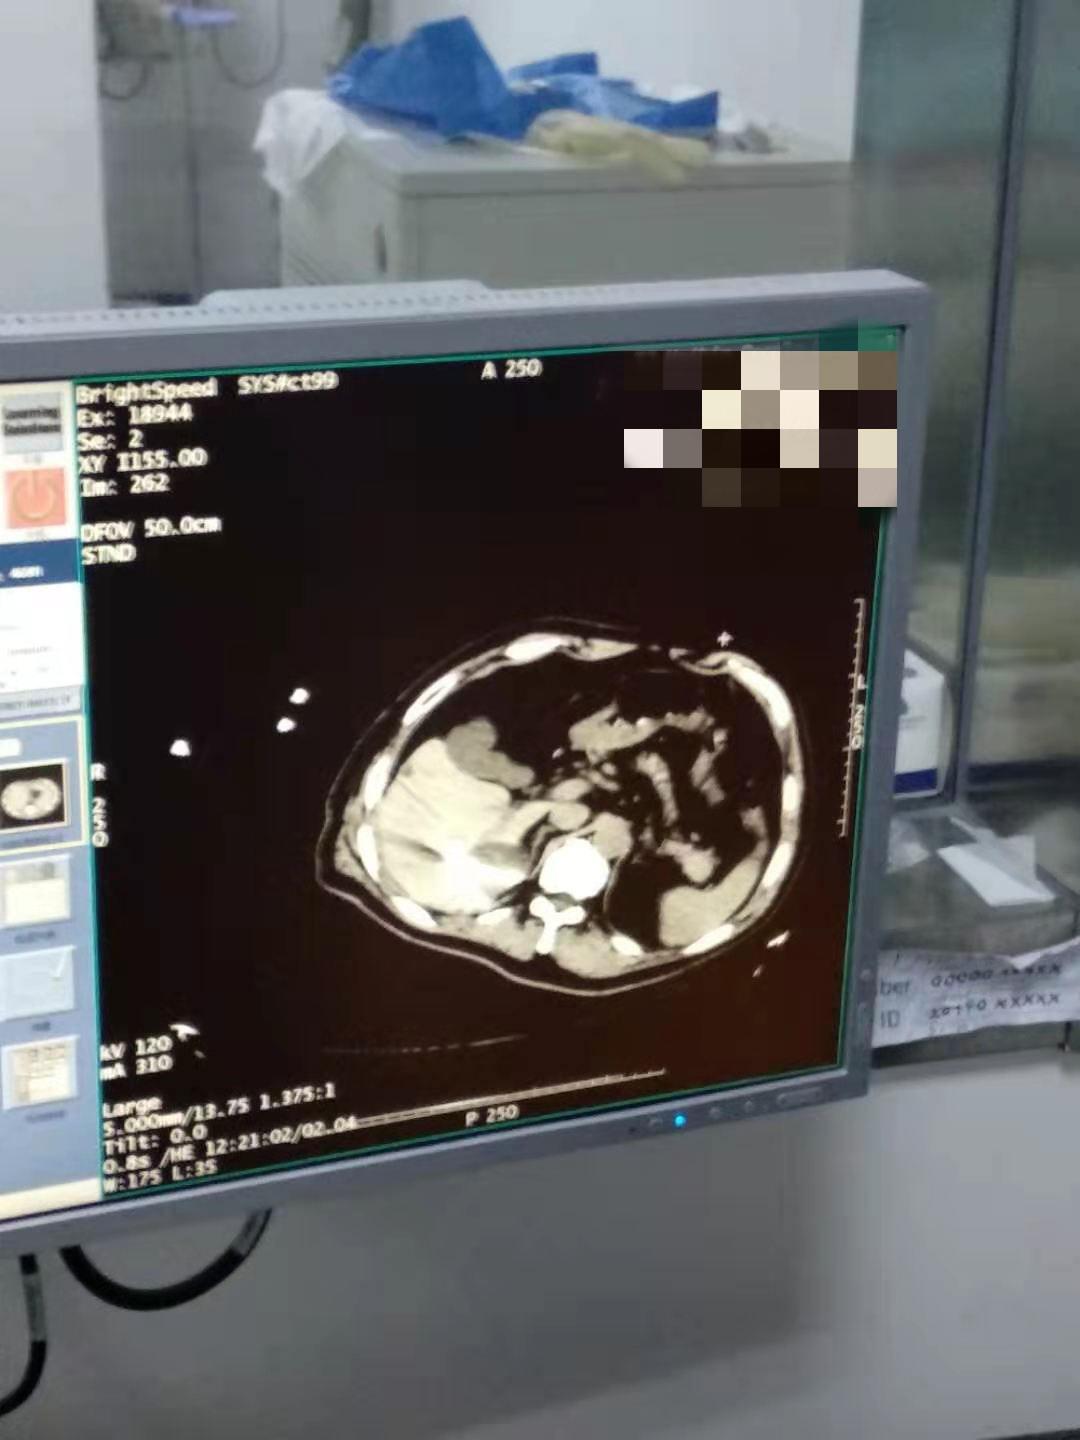

2021年2月份肝部氩氦刀手术